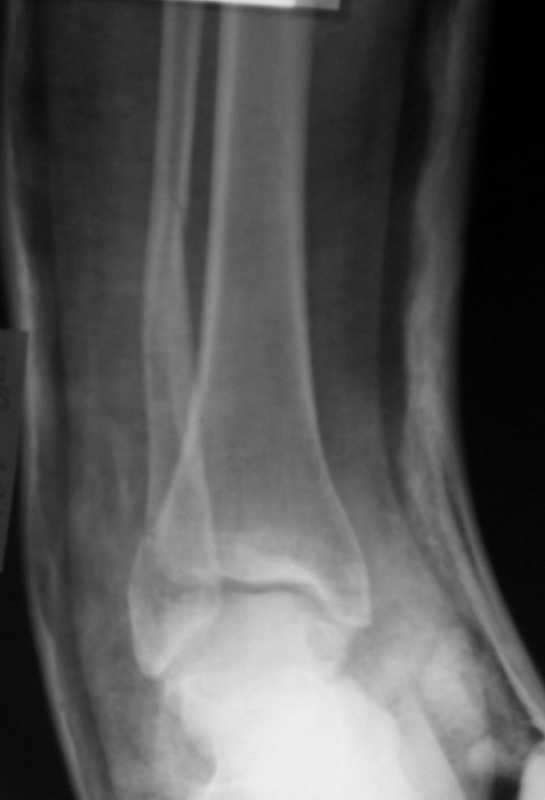

Пациентка, 30 лет с таким переломом. Произвел репозицию.

Теперь думаем, то ли так оставить, или все-таки, выполнить остеосинтез согласно рекомендациям АО? Хотелось бы услышать мнение коллег -- С ув. Sergey Melashenko